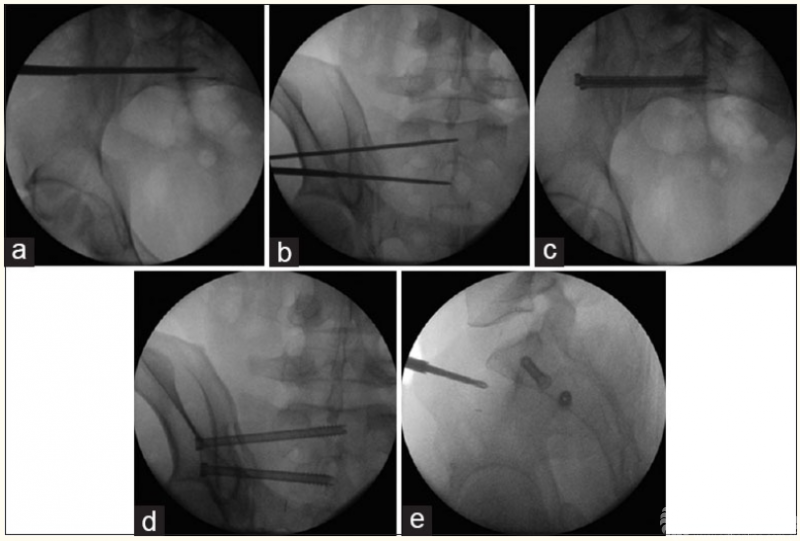

2、骨盆髋臼骨折的机器人辅助手术